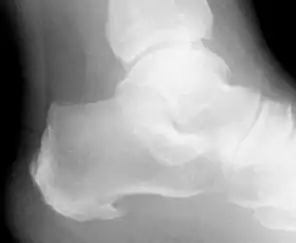

خار پاشنه (به انگلیسی: calcaneal spur) یا خار زیرین پاشنه یکی از ریشههای برجسته دردهای پیرامون پاشنه است خود این خار در حالت سرشتی، به گونه برجستگی استخوانی کوچکی درمحل چسبندگی آرنگ کف پا Plantar Fascia به استخوان پاشنه هست. در پی کوشندگی بسیار و راهپیمایی دراز و نیز در کسان فربه با پدید آوردن تب وتاب آرنگ کف پا، این خار برانگیخته شده و با رسوب کلسیم برجستگی بیشتری یافته ودردناک میگردد. این خار در عکسبرداری پرتو ایکس از پاشنه به روشنی آشکار میگردد. خار پشتی پاشنه در بخش پشت پاشنه و در جای چسبیدن تاندون آشیل پدید میآید و با اینکه کمتر از خار زیرین دیده میشود ولی در پی فشارهای پدید آمده و پیاده روی دراز و نیز در برخی بیماریها دردناک میگردد.

| خار پاشنه درعکسبرداری پرتو ایکس | |